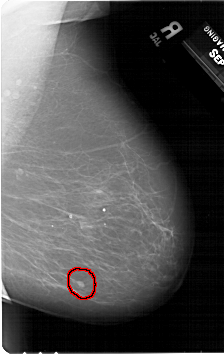

A_1354_1.RIGHT_CC

RIGHT_CC LINES 6871 PIXELS_PER_LINE 4456 BITS_PER_PIXEL 12 RESOLUTION 43.5 OVERLAY

FILE: A_1354_1.RIGHT_CC.OVERLAY

TOTAL_ABNORMALITIES 1

ABNORMALITY 1

LESION_TYPE MASS SHAPE OVAL MARGINS CIRCUMSCRIBED

ASSESSMENT 4

SUBTLETY 3

PATHOLOGY BENIGN

TOTAL_OUTLINES 1